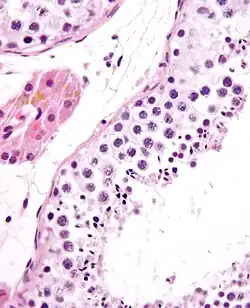

![]() Seminiferous tubule with maturing sperm. H&E stain. | |